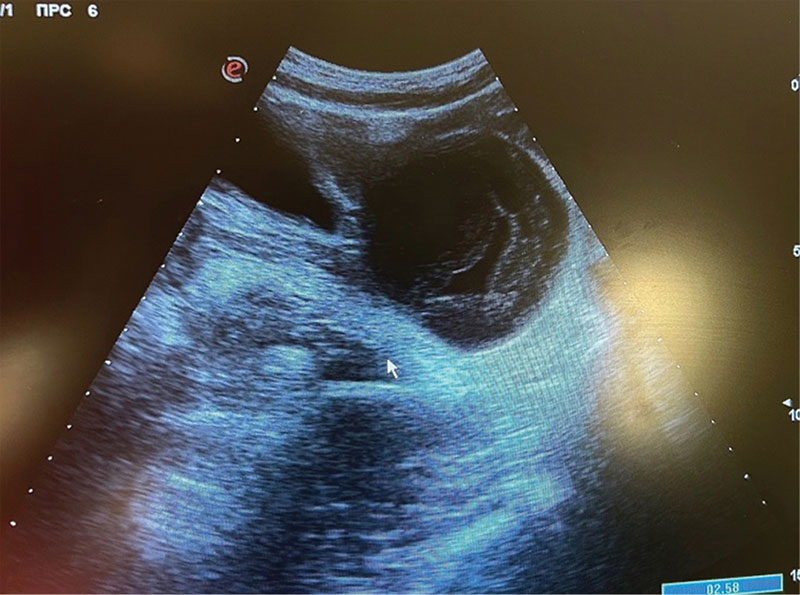

Рис. 6. Пациентка В., 13 лет: интраоперационная картина мягкого (нетугого) перекрута правых придатков матки

Интраоперационно обнаружен мягкий перекрут правых придатков матки на 180° вокруг собственной оси с вовлечением правого яичника за счет округлого образования диаметром до 12 см (рис. 6). Левые придатки матки без особенностей. Тело матки нормального размера, серозный покров гладкий, блестящий.